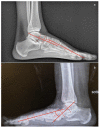

Adult acquired flatfoot deformity (AAFD) is a disorder caused by repetitive overloading, which leads to progressive posterior tibialis tendon (PTT) insufficiency. It mainly affects middle-aged women and occurs with foot pain, malalignment, and loss of function. After clinical examination, imaging plays a key role in the diagnosis and management of this pathology. Imaging allows confirmation of the diagnosis, monitoring of the disorder, outcome assessment and complication identification. Weight-bearing radiography of the foot and ankle are gold standard for the diagnosis of AAFD. Magnetic Resonance Imaging (MRI) is not routinely needed for the diagnosis; however, it can be used to evaluate the spring ligament and the degree of PTT damage which can help to guide surgical plans and management in patients with severe deformity. Ultrasonography (US) can be considered another helpful tool to evaluate the condition of the PTT and other soft-tissue structures. Computed Tomography (CT) provides enhanced, detailed visualization of the hindfoot, and it is useful both in the evaluation of bone abnormalities and in the accurate evaluation of measurements useful for diagnosis and post-surgical follow-up. Other state-of-the-art imaging examinations, like multiplanar weight-bearing imaging, are emerging as techniques for diagnosis and preoperative planning but are not yet standardized and their scope of application is not yet well defined. The aim of this review, performed through Pubmed and Web of Science databases, was to analyze the literature relating to the role of imaging in the diagnosis and treatment of AAFD.